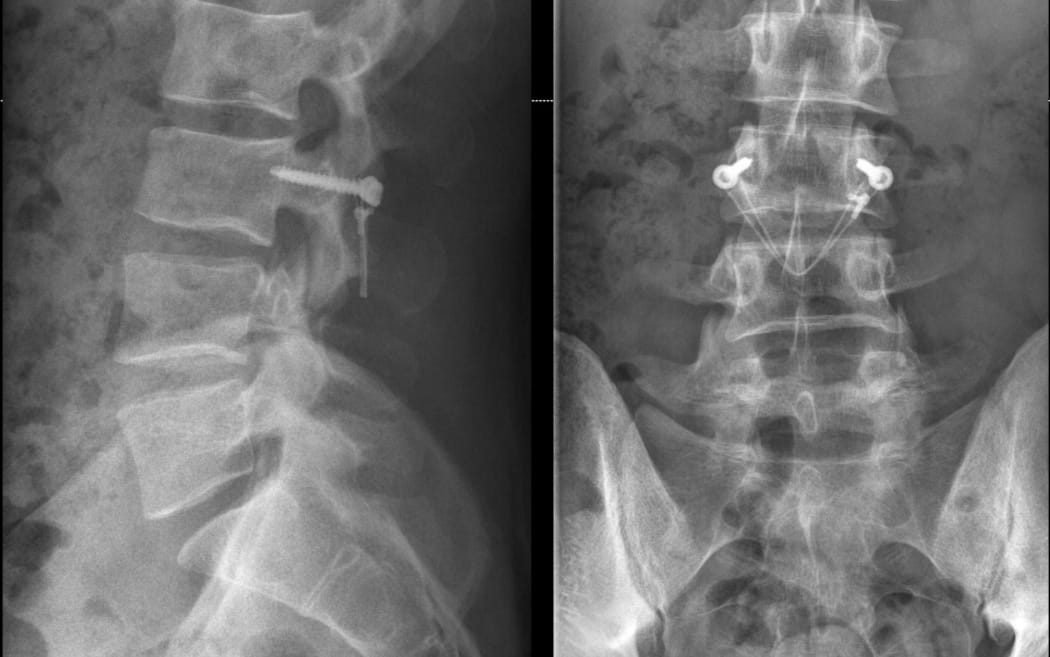

Orthopaedic spine surgeon Dr Rowan Schouten operates on a chronic back injury.

Orthopaedic spine surgeon Dr Rowan Schouten performs a back proceedure. Photo: Supplied/Dr Rowan Schouten

Schouten has slowly modified and "tweaked" the technique over time, but the "essence of it is still the same".

"Technology has changed quite a lot, even in the last 5-10 years," he said. "We have computer navigation in theatre that helps us put everything that we need to insert accurately.

"There's also a few other elements of the surgery that we've added in more recent years that I think are important for its success and to make sure that we deload that part of the spine that is so vulnerable to stress fractures.

"When players get back, not only do they have a fracture that's a bit more robust from all the surgery, but also the loads that are going through that spine are not as significant."